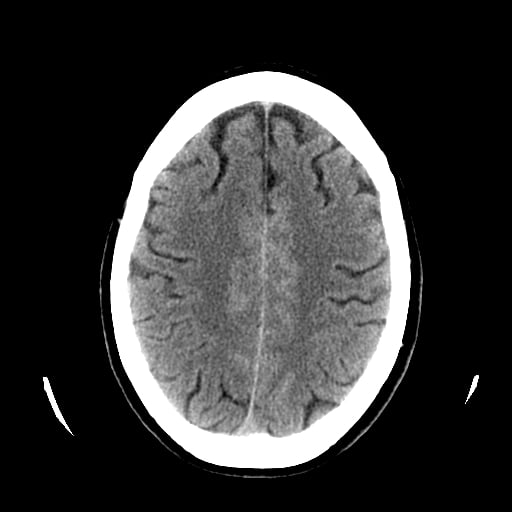

Exon-screening in Reversible Cerebral Vasoconstriction (RCVS)

Objectives: To investigate the genetic basis of RCVS using exome capture and deep sequencing.